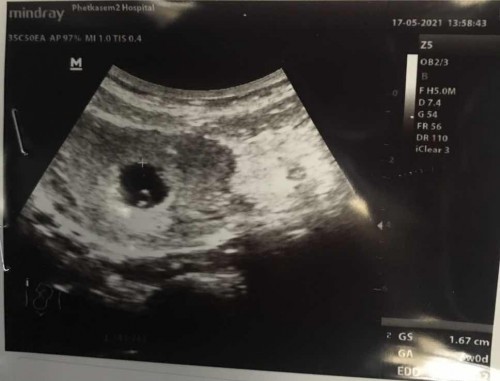

เรา6w เห็นไข่แดง เจอตัวน้อง หัวใจเต้นแล้วค่ะแต่น้องตัวเล็กมากๆ 0.20เองค่ะ ปัจจุบัน9wค่ะ คุณแม่อดใจรออีกนิดนะคะ 🥰💗

ภาพเหมือนบ้านนี้เลยค่ะถ้าเป็นแบบนี้8Wก็น่าจะเห็นตัวแล้วก็หัวใจน้องแล้วนะค่ะแม่

ภาพซาวตอน8สัปดาห์ ก็ประมาณนี้ค่ะ